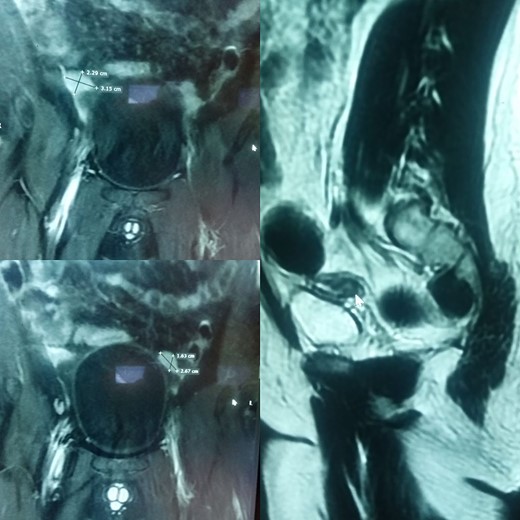

His ultrasound demonstrated an empty scrotum and the testes were not detected in any ectopic location including the inguinal canal and pelvis bilaterally. Subsequently, a computed tomography (CT) scan with IV contrast was performed, which revealed well-defined enhancing areas in the lower abdomen measuring 2.5 cm × 2 cm on the left and 2.5 cm × 1.6 cm on the right correlating to the undescended testes. Furthermore, a soft tissue density structure likely to be a rudimentary uterus measuring 5.8 cm × 4 cm was seen posterior to the urinary bladder (Fig. 1).

(A) and (B) are radiographic images showing well-defined enhancing areas in the lower abdomen likely to be testes. (C) shows the presence of a soft tissue density structure, i.e. a rudimentary uterus posterior to the urinary bladder.